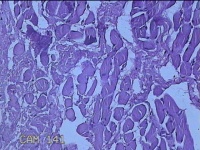

性别

男

年龄

26岁

临床诊断

皮脂腺囊肿

一般病史

发现前额部结节3年余。

标本名称

前额部结节

大体所见

灰白暗红色结节0.8x0.7x0.2cm一个,表面糜烂。

图1